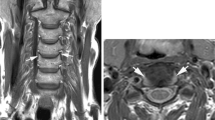

Significant stenosis/T2 signal and clinical myelopathy: 72-year-old male who presented with progressive weakness in the hands/arms/legs, now requiring wheelchair for mobilization. MRI C spine demonstrated multilevel cervical stenosis (Fig. 9.3).

Minimal stenosis/T2 signal and clinical myelopathy: 44-year-old female who presented with frequent falls, hand dexterity issues, and bilateral Hoffman’s signs. MRI C spine demonstrated C5/C6 canal stenosis. Though there was slight CSF signal posterior to the spinal cord, there was a concern for dynamic spinal cord damage with the pronounced herniated disc and the loss of cervical lordosis. After an ACDF C5/C6, she noted improvement with balance and with fine motor skills (Fig. 9.4).

71-year-old male who presented with bilateral hand numbness in the first to third digits, where workup included MRI C spine and electromyography. The former demonstrated severe stenosis at C3/C4 (arrow); the latter was consistent with bilateral carpal tunnel syndrome. He underwent carpal tunnel releases, with improvement of symptoms

44-year-old female who presented with frequent falls, hand dexterity issues, and bilateral Hoffman’s signs. MRI C spine demonstrated C5/C6 canal stenosis (arrow). Though there was slight CSF signal posterior to the spinal cord, there was a concern for dynamic spinal cord damage with the pronounced herniated disc and the loss of cervical lordosis. After an ACDF C5/C6, she noted improvement with balance and with fine motor skills